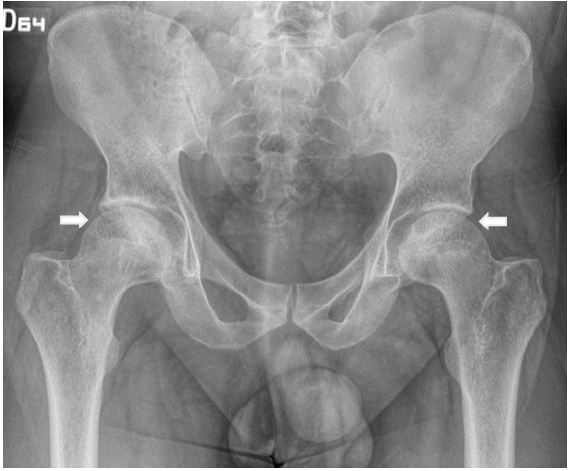

We report a case of a 31 years-old male, with medical history of obesity (BMI 31) and severe pneumonia by CoViD-19 previous, during hospital stay requires intravenous steroids (total dose 60 mg of dexamethasone) and immobilization secondary prostration at least one month. He consults one year later for pain in left groin and secondary limp. Physical examination showed abduction, external rotation and flexion diminished in left hip. Initial X-ray evidence areas of low density both femoral heads (Figure 1). Following study with simple Magnetic Resonance Image (MRI) (Figure 2) showed right hip with changes of necrotic bone without edema, a calculated Kerboul angle of 274o, in left hip edema and areas on necrotic bone, with an anterocentral subchrondral bone fracture of femoral head, Kerboul angle of 257º.

Figure 1: Bilateral hip X-ray Anterior-posterior view showing low density zones (arrows) in both femoral heads. Following study with simple magnetic resonance imagen (MRI) (Figure 2) showed right hip with changes of necrotic bone without edema, a calculated Kerboul angle of 274o, in left hip edema and areas on necrotic bone, with an anterocentral subchrondral bone fracture of femoral head, Kerboul angle of 257o.